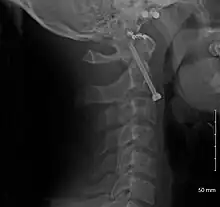

Fracture of dens

Repair of a dens fracture

Fractures of the dens, not to be confused with Hangman's fractures, are classified into three categories according to the Anderson Alonso system:

• Type I fracture - Extends through the tip of the dens. This type is usually stable.

• Type II fracture - Extends through the base of the dens. It is the most commonly encountered fracture for this region of the axis. This type is unstable and has a high rate of non-union.

• Type III fracture - Extends through the vertebral body of the axis. This type can be stable or unstable and may require surgery.